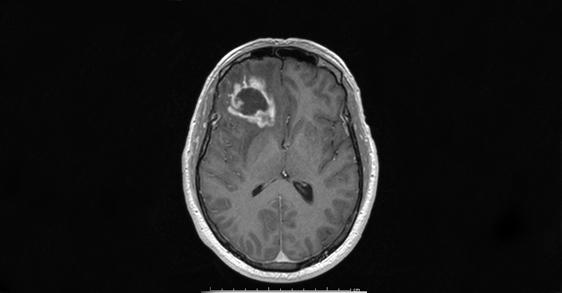

Biological clocks throughout the body play a major role in human health and performance, from sleep and energy use to how food is metabolized and even stroke severity. Now, Texas A&M University researchers found that circadian rhythms could hold the key to novel therapies for glioblastoma, the most prevalent type of brain cancer in adults--and one with a grim prognosis.

Scientists in the Texas A&M Center for Biological Clocks Research (CBCR) determined that the timed production of a particular protein, associated with tumor proliferation and growth, is disrupted in glioblastoma cells, and they believe that this may lead to a more effective technique to treat the cancerous cells without damaging the healthy surrounding tissue. These findings, which were supported in part by the National Institutes of Health, were published today (Jan. 10) in the international journal BMC Cancer .

Glioblastomas gained some attention this summer when Senator John McCain was diagnosed with the condition. "A big reason for poor prognosis for patients with this aggressive type of tumor is that the glioblastoma cells rapidly and unabatedly invade and disrupt the surrounding brain cells," said Gerard Toussaint, MD, a clinician and assistant professor at the Texas A&M College of Medicine who specializes in glioblastoma. Current treatments--including chemotherapy, surgical resection, immunotherapy and radiation--are largely ineffective in prolonging life expectancy beyond 18 months.